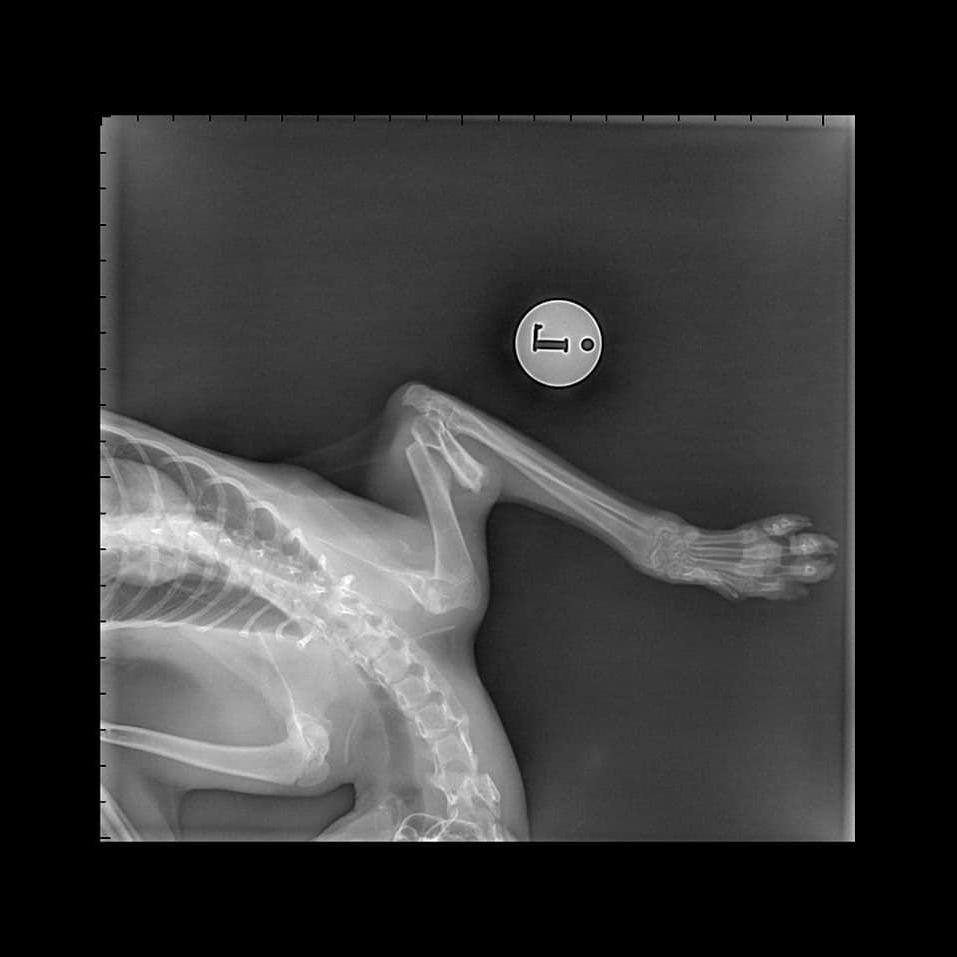

Kvido je mladý tuláček, který začal chodit k jedné paní na krmení a ta si po nějaké době všimla že má zraněnou packu. Po návštěvě veteriny se zjistilo, že se jedná o zlomeninu pod kloubem. To však nelze snadno fixovat a proto musel podstoupit operaci na klinice v Brandýse, která se podařila.

Kvido momentálně potřebuje rehabilitovat pacičku, což jeho dočaskářka ráda ukáže. Packu zcela nenatáhne, takže ji nepoužívá na plno. Jinak je to ale kocourek, který nepotřebuje v běžném pohybu nijak zvlášť pomáhat. Hlavní pro něj tedy je najít trpělivé páníčky, kterým nebude za těžko s ním cvičit a nebudou řešit to, že kocourek kulhá. Důležité totiž je, že vrací lásku na max :)

- potřebuje rehabilitovat přední packu